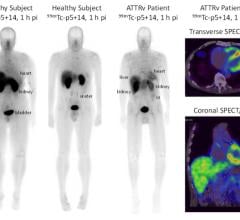

“For some patients with head and neck cancer, removal and pathological examination of lymph nodes draining a primary tumor is an important diagnostic evaluation,” said Libero Marzella, M.D., Ph.D., director of the division of medical imaging products in the FDA’s Center for Drug Evaluation and Research. “To use Lymphoseek, doctors inject the drug into the tumor area and later, using a handheld radiation detector, find the sentinel lymph nodes that have taken up Lymphoseek’s radioactivity.”

For this new indication, Lymphoseek’s safety and effectiveness were established in a clinical trial of 85 patients with squamous cell carcinoma of the lip, oral cavity and skin. All patients were injected with Lymphoseek. Surgeons subsequently removed suspected lymph nodes — those identified by Lymphoseek and those based upon tumor location and surgical practice — for pathologic examination. Results showed that Lymphoseek-guided sentinel lymph node biopsy accurately determined if the cancer had spread through the lymphatic system.

The sNDA submission included data from the NEO3-06 Phase 3 study. That showed statistical significance of Lymphoseek’s ability to correctly identify patients with pathology-positive lymph nodes compared with multiple level lymph node dissection and pathology assessment. The Phase 3 trial NEO3-06 was a prospective, open-label, multicenter, within-patient study. It was designed to identify sentinel lymph nodes and determine the false negative rate (FNR) associated with Lymphoseek-identified SLNs relative to the pathological status of non-SLNs in head and neck and intraoral squamous cell carcinoma. The primary endpoint for the NEO3-06 trial was based on the number of subjects with pathology-positive lymph nodes following a multiple level lymph node dissection and required a minimum of 38 subjects whose lymph nodes contained pathology-confirmed disease. Of the more than 80 subjects enrolled in the NEO3-06 trial, 39 subjects were determined to have pathology-positive lymph nodes. Results demonstrated that Lymphoseek correctly identified 38 of these 39 patients, for an overall FNR of 2.56 percent, which met the predefined statistical threshold. These findings indicate that Lymphoseek accurately identified SLNs in these trial subjects, and is likely to be predictive of overall node pathology status. Moreover, multiple level nodal dissection of patients in the trial with cancer-positive lymph nodes led to an average removal of 38 lymph nodes per patient, whereas Lymphoseek on average led to the removal of approximately four lymph nodes, representing a substantial reduction in potential morbidity for patients with head and neck cancer undergoing single lymph node biopsy.